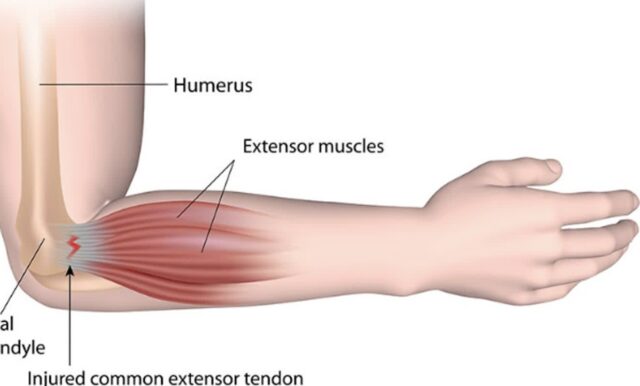

내측상과염 팔꿈치 안쪽 통증 원인 및 증상 골퍼 엘보 의심된다면